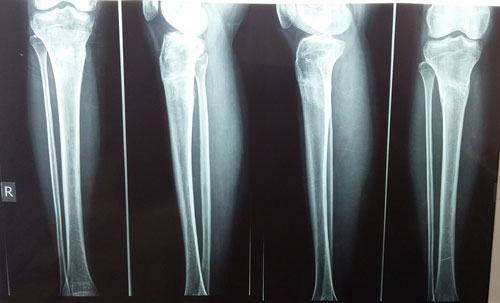

Пациентка Маня. (33 г.)

Дата операции 25.03.2015г.

Исходник.